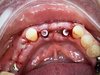

· Проведение хирургических вмешательств с фокусом на полную реабилитацию (All-on-4/6) с немедленной нагрузкой.

· Хирургическое лечение полного спектра случаев: от единичных имплантаций до комплексных реабилитаций.

· Полный цикл ортопедической реабилитации: от подготовки (имплантация, НКР) до фиксации постоянных конструкций (цирконий, металлокерамика, съемные протезы).

· Комплексная имплантация: All-on-4, All-on-6 (FP-1), одномоментная и отсроченная имплантация.

· Работа с системами: Nobel Biocare, Straumann, Ankylos (Dentsply Sirona), Astra Tech, Osstem, Dentium, Bicon, AWI.